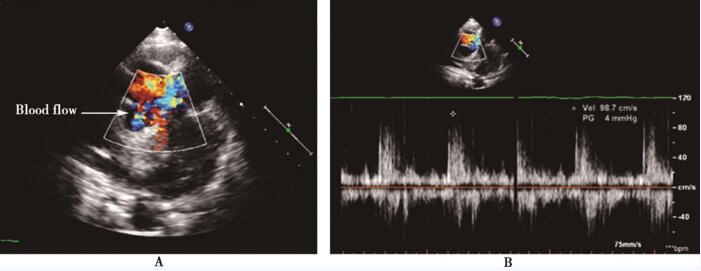

入院后进一步完善超声心动图:左心房上方探及一等回声团块,大小3.6cm×3.5cm,回声欠均匀、边界不清晰,部分与左心房壁、主动脉后壁粘连;升主动脉后壁距主动脉瓣约1.2cm处探及回声失落,大小约0.7cm,后方为无回声区,该无回声区位于占位右前方,彩色多普勒于回声失落处探及升主动脉与无回声区收缩期双向血流交通信号,最大流速约0.9m/s;占位左侧为肺动脉主干、右肺动脉,主肺动脉、右肺动脉右侧边界显示不清晰,彩色多普勒示肺动脉内血流未见明显异常。结论:左心房上方占位,性质待查 (肿瘤?血栓?),占位与主动脉后壁粘连,假性动脉瘤形成可能性大,不除外占位累及肺动脉主干、右肺动脉可能(图50-1、50-2)。

图50-2 入院超声心动图 A:升主动脉短轴切面示主动脉假性动脉瘤内血流信号; B:脉冲多普勒探查破口处血流速度。Blood flow:血流

本例患者平素体健,4个月前无明显诱因出现胸闷、憋气并于活动后加重,考虑为继发性肺结核、结核性心包炎,予异烟肼、利福平、乙胺丁醇抗结核并穿刺置管引流心包积液。2周前于当地医院行超声心动图偶然发现左心房内占位病变,经食管超声心动图提示主动脉假性动脉瘤可能。到我院就诊后,复查超声心动图提示左心房后上方一混合回声团块,内有2.5cm×1.7cm无回声区,经仔细扫查并增加彩色多普勒,发现无回声区与主动脉后壁破口相通,脉冲多普勒探查到无回声区内收缩期血流信号、峰值流速约98cm/s。此时,主动脉假性动脉瘤诊断基本确立。由于混合斑块体积较大致压迫右肺动脉、左心房和周围组织,加之患者无明确胸部外伤病史,暂不敢贸然下结论,提示假性动脉瘤形成可能性大,不除外占位累及肺动脉主干、右肺动脉可能。进一步行胸部CT提示升主动脉近段后壁破口、向后突出、假性动脉瘤形成,同时排除纵隔占位病变。